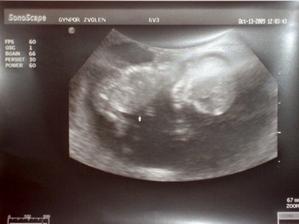

- 13.10.09 boli sme na sono a dostali sme aj nasu prvu fotku a nastastie vsetko vyzera byt v poriadku